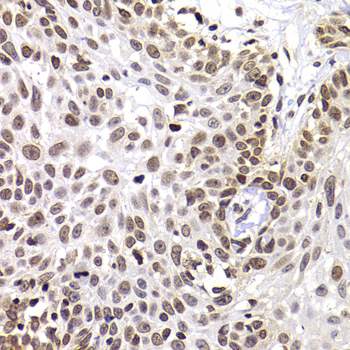

Immunohistochemistry of paraffin-embedded human well-differentiated squamous skin carcinoma using PHIP antibody at dilution of 1:100 (40x lens).

Immunohistochemistry of paraffin-embedded human kidney cancer using PHIP antibody at dilution of 1:100 (40x lens).

Immunohistochemistry of paraffin-embedded mouse cancer using PHIP antibody at dilution of 1:100 (40x lens).